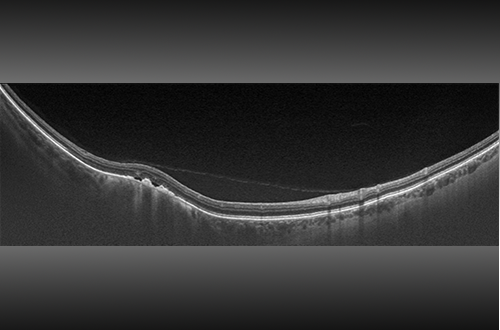

Swept Source OCT (SS OCT) is an advanced form of optical coherence tomography (OCT), a non-invasive imaging method that uses light to capture detailed cross-sectional images of the eye's inner workings. Unlike Spectral Domain OCT (SD-OCT), SS OCT utilizes a special laser that covers a broad range of frequencies, enabling quicker scans, better penetration into deeper tissues, and reduced signal loss.

OCT operates on the principle of low coherence interferometry. This technique measures how light, reflected off the eye's internal structures and a reference mirror, interferes with each other. The pattern of this interference reveals the depth of the structures being examined. By moving the light beam across the eye, OCT can compile these reflections into detailed 2D or 3D images.

There are several OCT methods, including Time Domain (TD OCT), Spectral Domain (SD OCT), and Swept Source (SS OCT). TD OCT changes the optical path by moving the reference mirror, capturing the interference with a single photodetector. SD OCT keeps the reference mirror stationary, using a spectrometer to analyze the interference signal across the light spectrum. SS OCT also keeps the mirror stationary but stands out by using a tunable laser that sweeps across wavelengths, with a photodetector capturing the interference signal in sync with the laser. This approach allows SS OCT to offer faster, clearer, and more detailed images of the eye's interior, making it a powerful tool in eye care diagnostics.

- Better Depth Resolution: SS OCT's longer wavelengths (1.0–1.3 micrometers) allow it to see deeper into the retina, up to 3 millimeters, revealing more of the eye's internal structures like the choroid and optic nerve head compared to SD OCT's 2 millimeters depth.

- Clearer Images Throughout: Unlike SD OCT, SS OCT maintains image clarity at various depths without the issue of spectral roll-off, ensuring sharp, consistent quality from the surface down to deeper layers.

1. SS OCT offers high-resolution, contrast-rich imaging to closely examine the retina's layers and tiny blood vessels, including using OCT angiography to spot changes in blood flow. It's key for diagnosing and tracking conditions like age-related macular degeneration, diabetic retinopathy, and more. SS OCT also excels in analyzing the front part of the eye (cornea, iris, lens), measuring their details and spotting issues like cataracts and glaucoma.